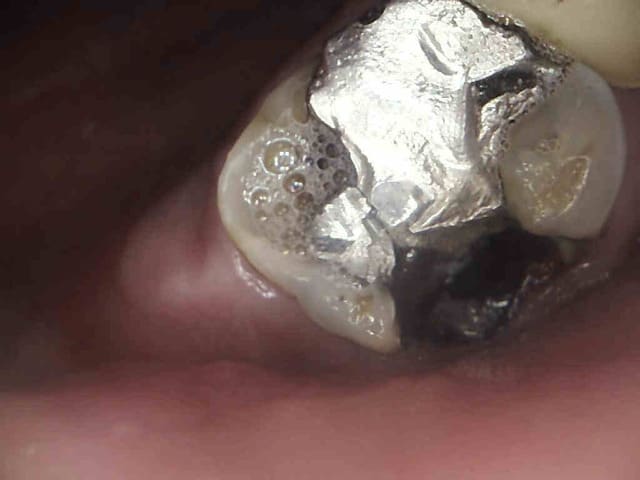

Ton plombier et ses 80 euros peut aller se rhabiller, patiente CMU encore, je ne pense pas que des composites à 2 balles soient indiqués.

2 v0xtrf - Eugenol

3 lwdn4a - Eugenol

1 uql9qu - Eugenol